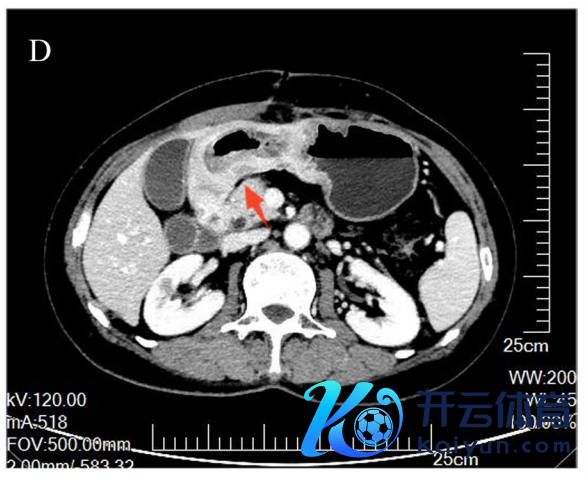

术后胃部CT:窦区胃壁增厚伴周围淋凑趣儿(图1D,E)。

图1D,E. 术后胃CT露馅胃窦胃壁增厚,最厚处直径约22 mm,累及管腔环周,长约150 mm,周围淋凑趣儿教导术后梗阻症状彰着缓解。